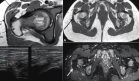

La tomografía axial computarizada (TAC) cerebral simple reveló una lesión temporal con hemorragia intracerebral espontánea, desplazamiento de línea media y edema perilesional.

Los diagnósticos diferenciales incluyeron tumor cerebral (glioblastoma, astrocitoma) y aneurisma de arteria cerebral media. Ante estos hallazgos, se programó una craneotomía de emergencia para drenaje.

Durante la craneotomía se identificó una masa tumoral amarillenta, de consistencia dura, con áreas necróticas sugestivas de astrocitoma. El postoperatorio transcurrió sin complicaciones, y una TAC de control confirmó resección tumoral satisfactoria.